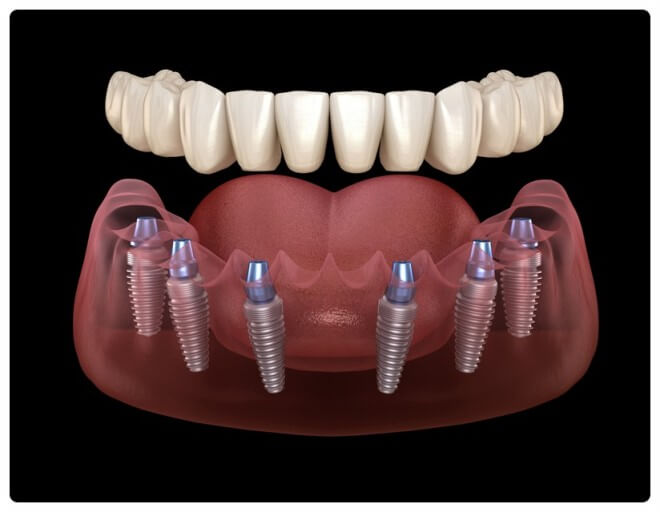

임플란트는 쉽게 말씀드리면 치아를 제거한 부위에 인공적으로 만든 치아를 즉, 임플란트를 식립 하는 시술입니다.

치과임플란트 급여안내 목적 건강보험 보장성 강화의 일환으로 노인의 저작기능 개선을 통한 건강증진 및 삶의 질 향상을 도모하기 위함 치과임플란트란? 치아가 빠진 경우 인공치아를 심어서